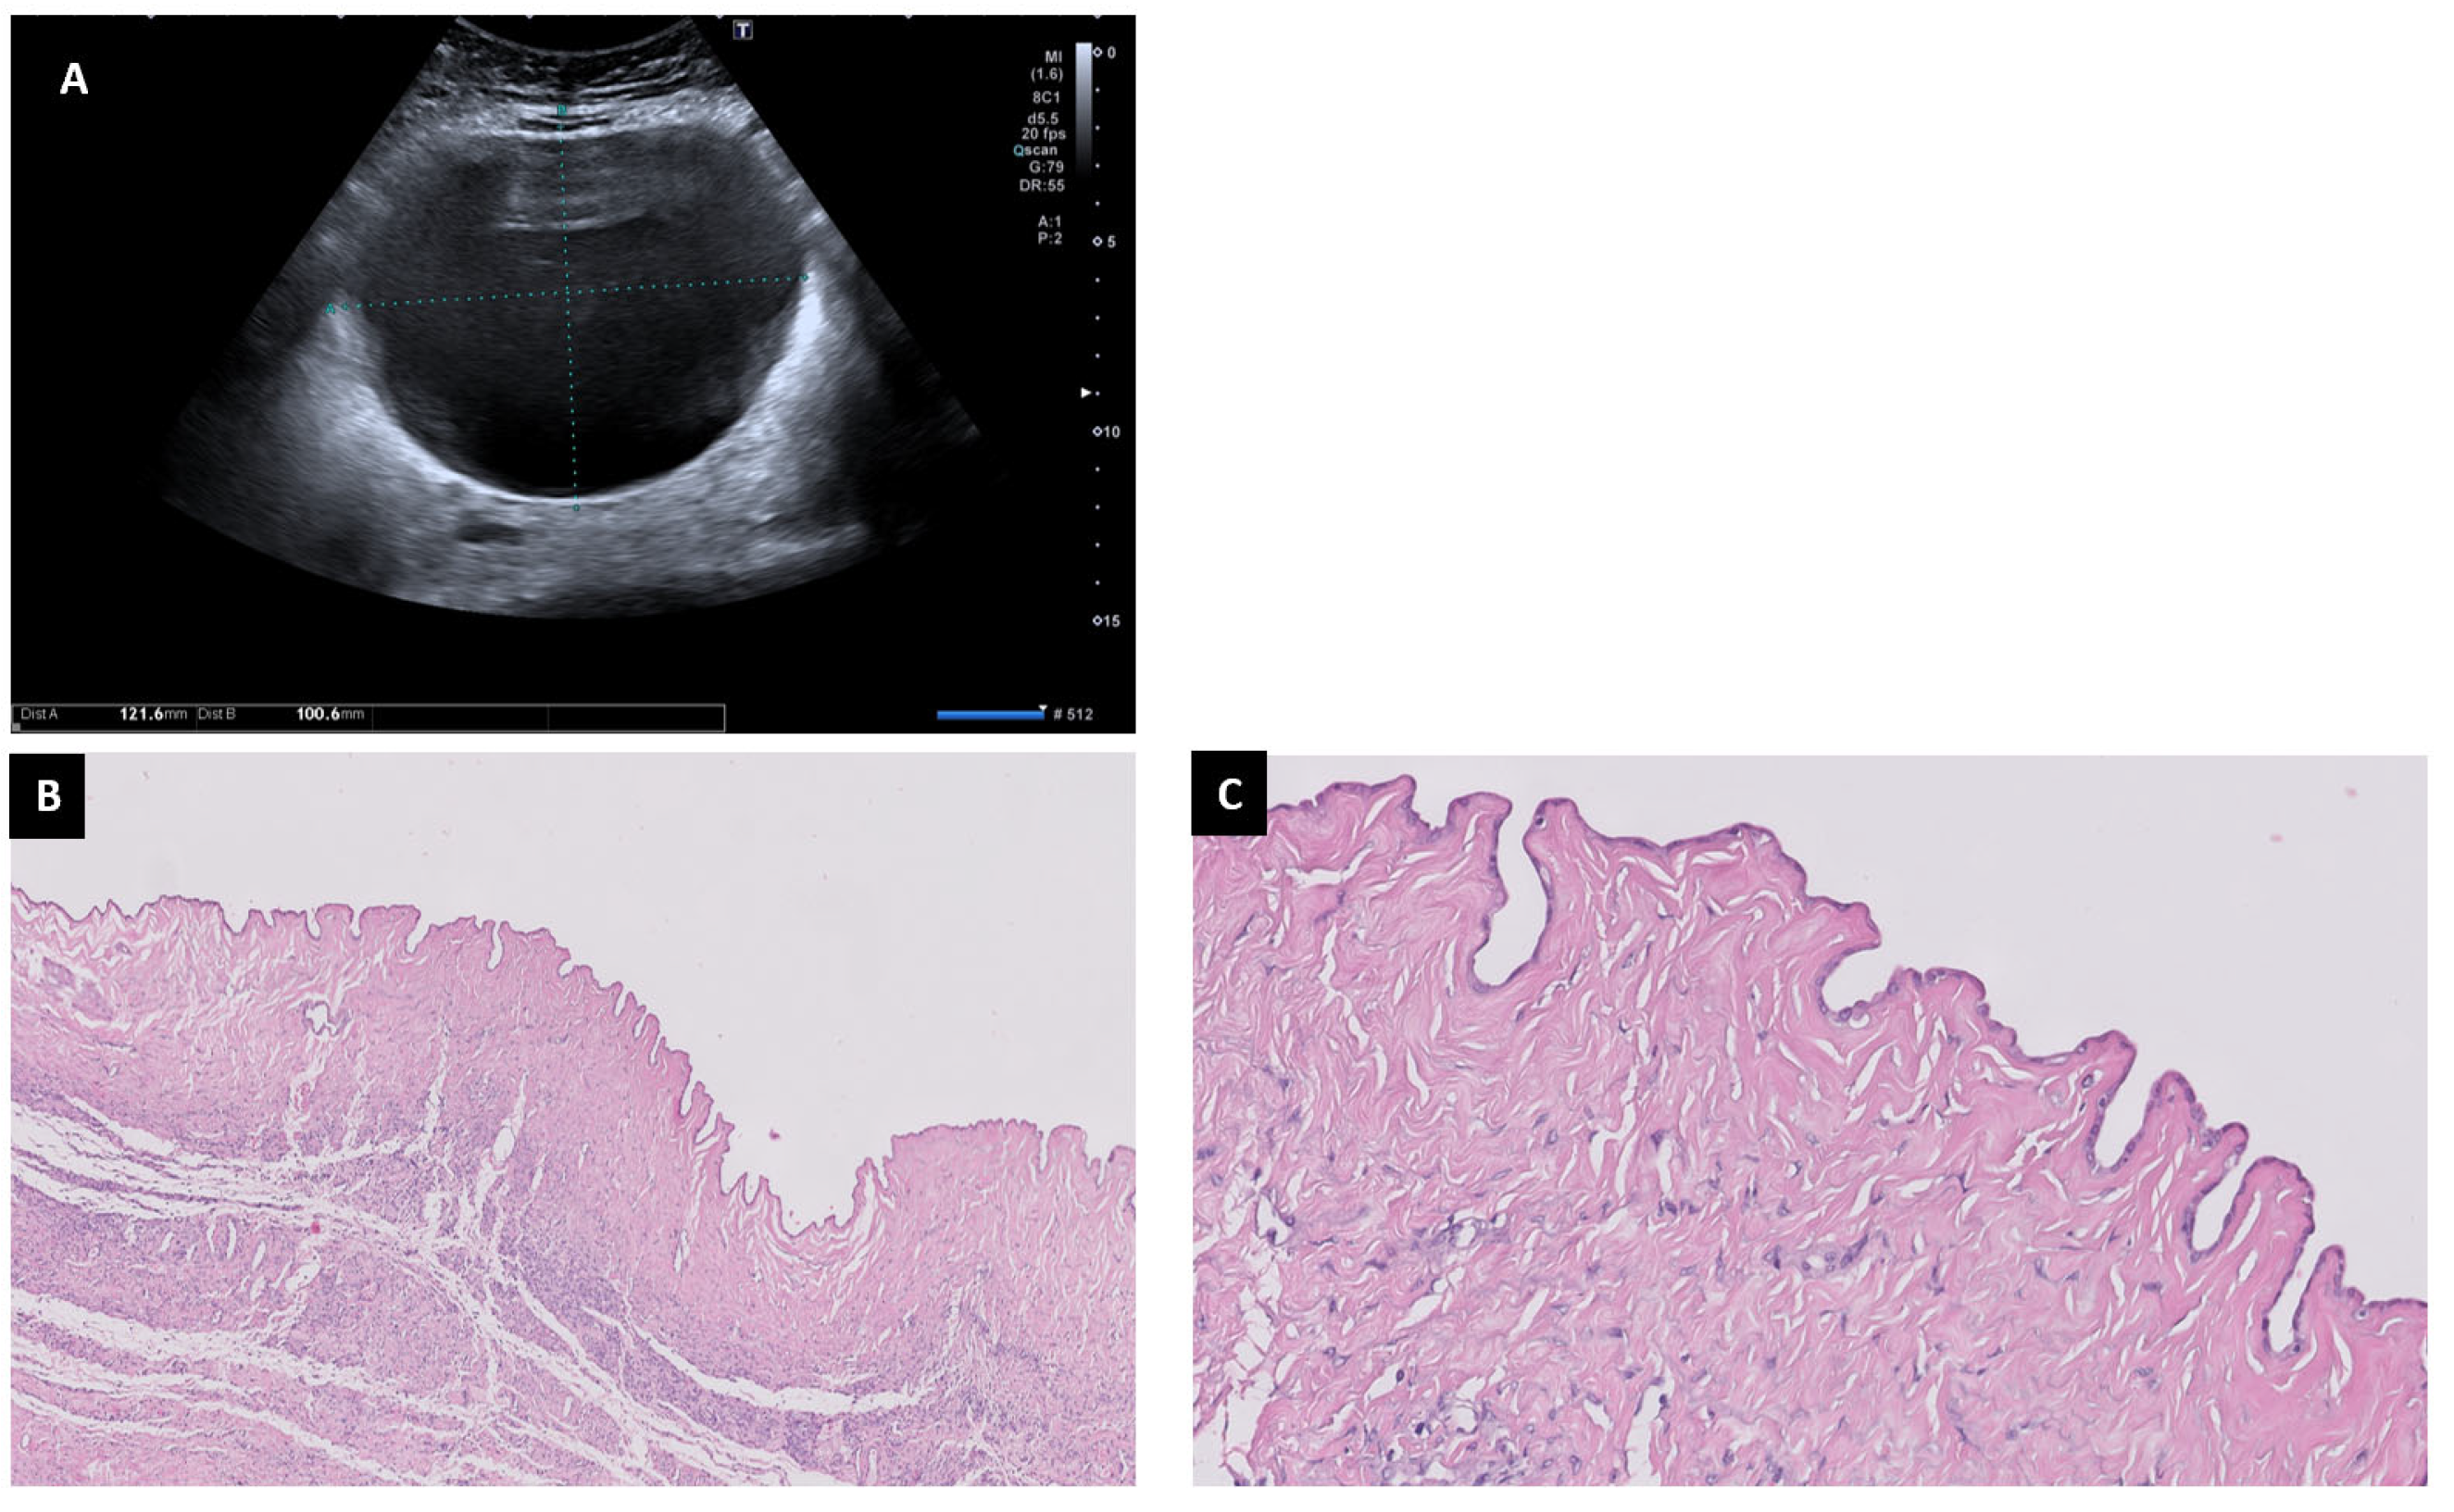

6.4. Mucinous Cystadenoma

6.5. Serous Cystadenoma